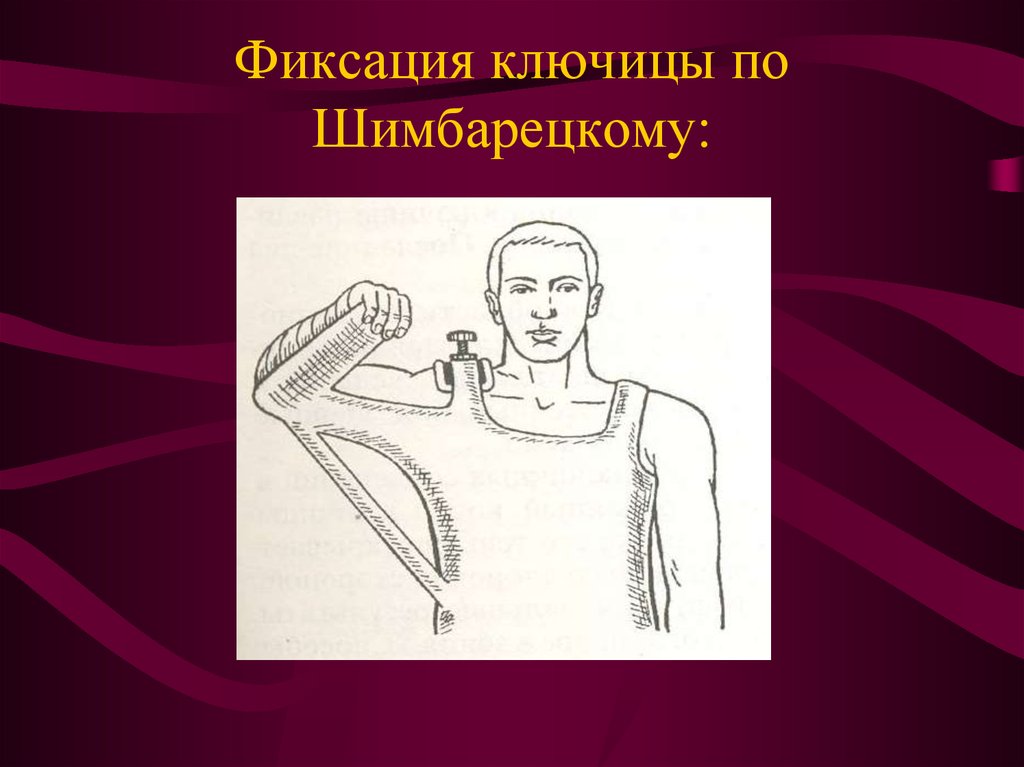

Вывихи и переломы ключицы презентация - 85 фото